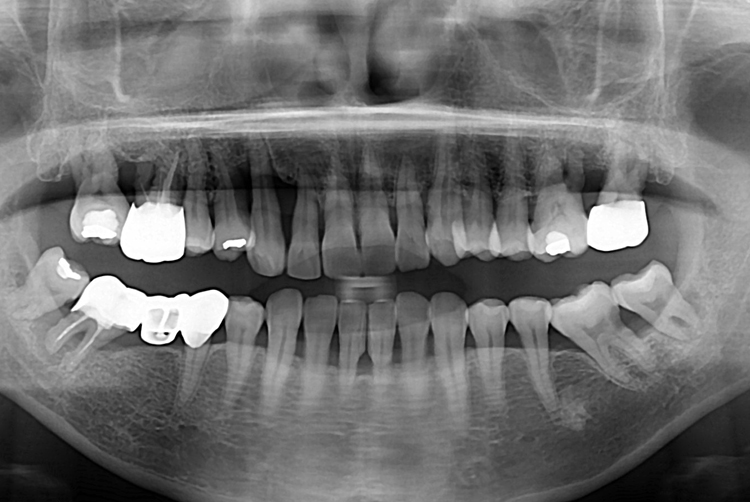

[임플란트] 어금니 임플란트

치료전 : 2019-02-19